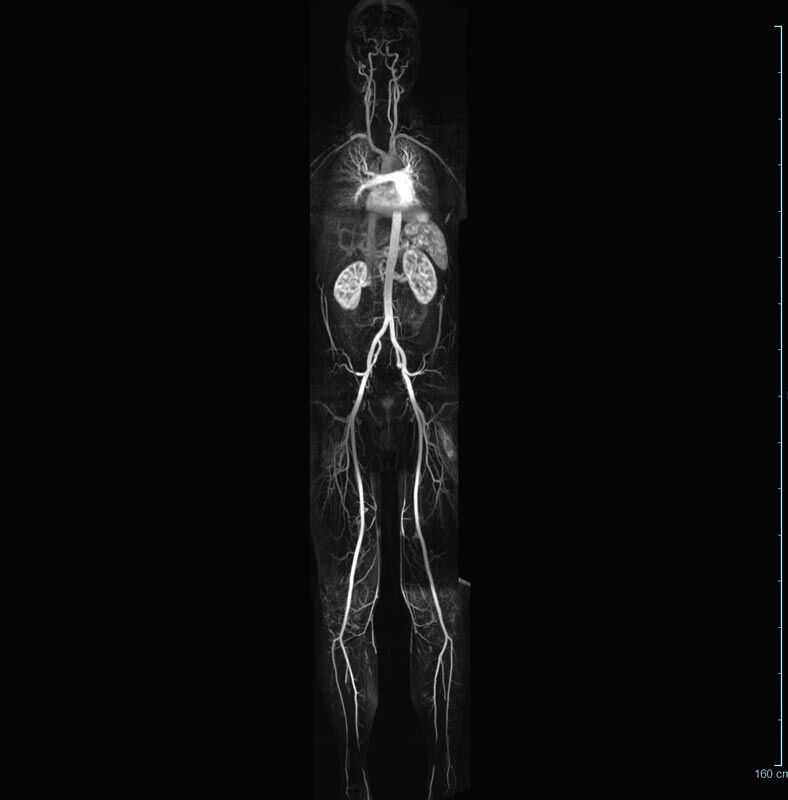

MR-Angiografie (MRA)

• MR-Angiografie ohne Kontrastmittel

• Time of Flight (TOF)-Angiographie

Je nach Fragestellung und Körperregion Gefäßdarstellung ohne Kontrastmittel bei Kontrastmittelunverträglichkeit oder terminaler Niereninsuffizienz möglich.

• MR-Angiographie mit Kontrastmittel

• Erfassung arterieller und venöser Gefäße/Bypässe aller Körperregionen mit 3D-Rekonstruktion